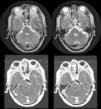

Vertebrobasilar dolichoectasia is a condition in which there is elongation and dilatation of the vertebral and basilar arteries. Few studies have been reported that focus on cases of trigeminal neuralgia (TN) secondary to vertebrobasilar dolichoectasia (VD) and treated by microvascular decompression (MD).

Patients and methodsA case is presented of trigeminal neuralgia caused by vertebral artery compression. An analysis of the microsurgical technique, as well as a systematic review of the literature about this uncommon nerve compression is performed, in order to investigate, by pooled case analysis, if MD is a good option for this type of patient.